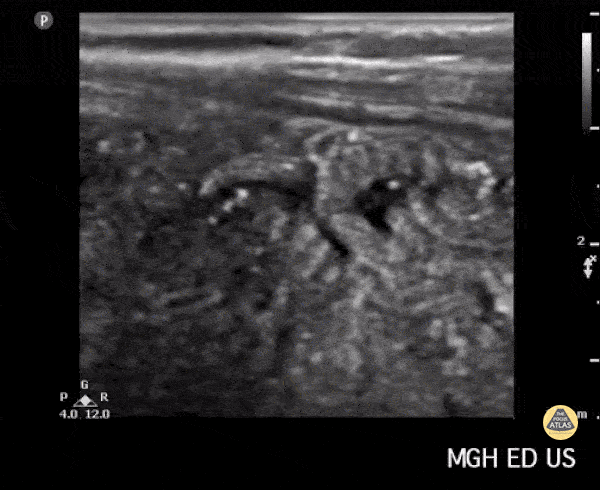

A two-year old with an intestinal nematode. Andrew Liteplo MD, RDMS - Massachusetts General Hospital Chief, Division of Ultrasound in Emergency Medicine Director, Emergency Ultrasound Fellowship